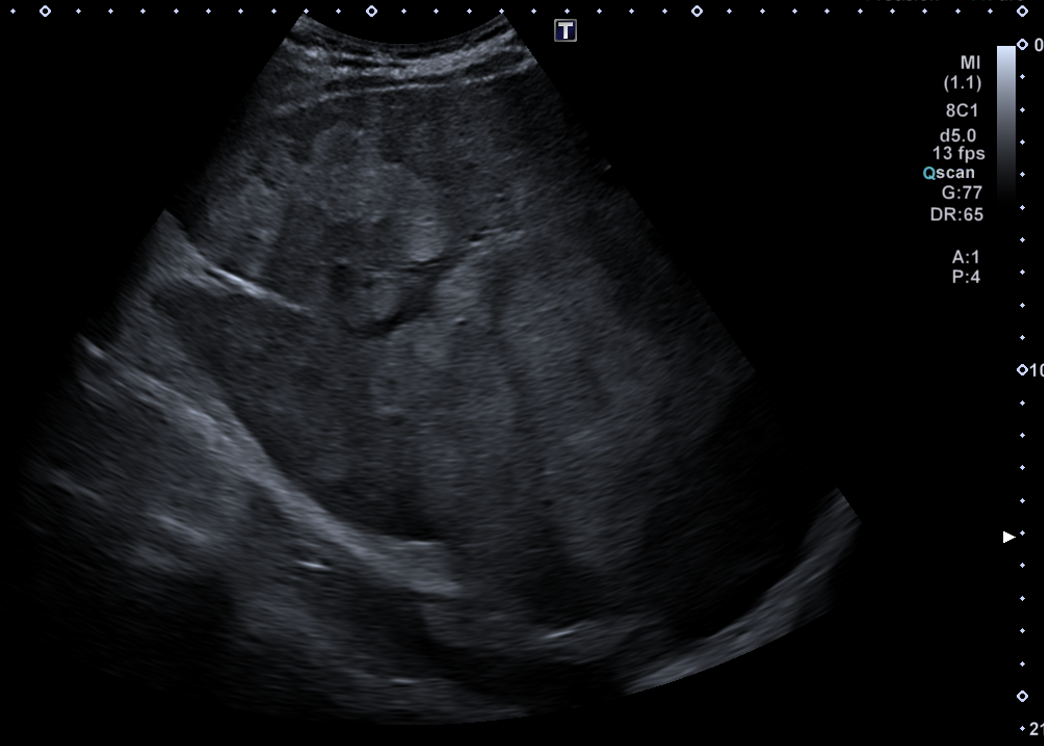

En ecografía en Centro de Salud: La práctica totalidad del parénquima hepático se encuentra sustituida por múltiples lesiones sólidas nodulares hiperecoicas, de predominio en el lóbulo hepático derecho, donde presentan tendencia a la confluencia y conforman una masa que alcanza los 13 cm de diámetro máximo. La vena porta es permeable y ectásica, con esplenomegalia. Ambos son signos de hipertensión portal.